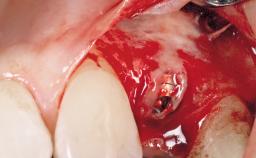

After the placement of three diameter-reduced two-piece implants the bone is augmented with autologous bone chips and DBBM particles to enlarge the crest volume. The surgery is completed with the application of two membrane layers and primary wound closure.

For soft tissue management, the initial healing caps are replaced with a longer type 8 weeks after implant placement in a second intervention before prosthodontic treatment is initiated.